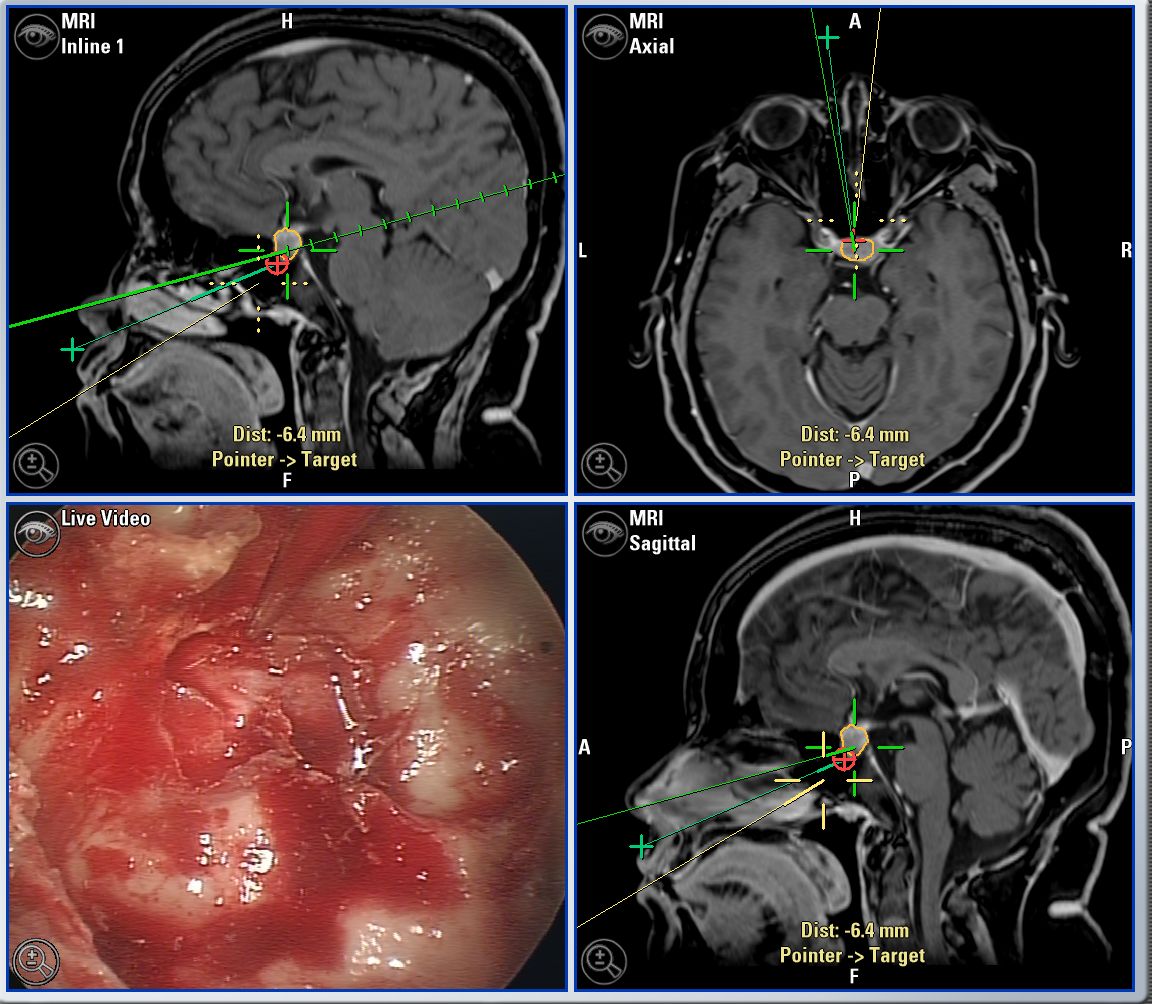

Microcirugía de base craneal